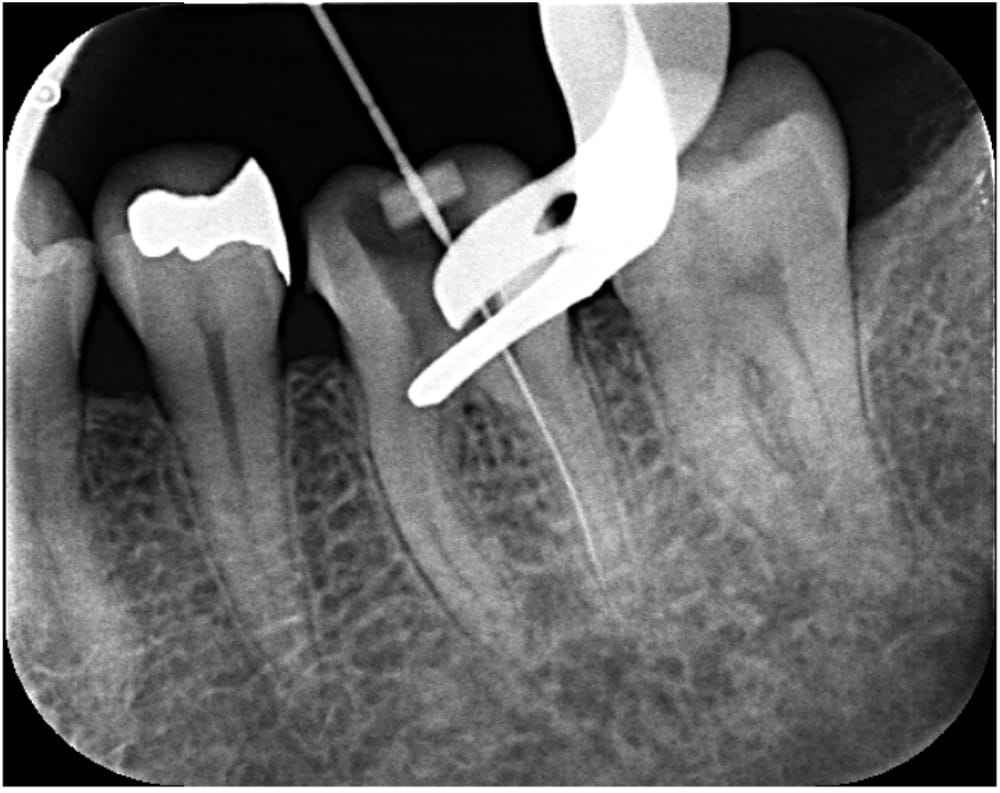

2回目の来院時には、当初抱えていた強い痛みはかなり軽減していました。

根管内を徹底的に清掃し、充填のためのガッタパーチャポイントを試適し、根管充填+コア築造まで完了しました。